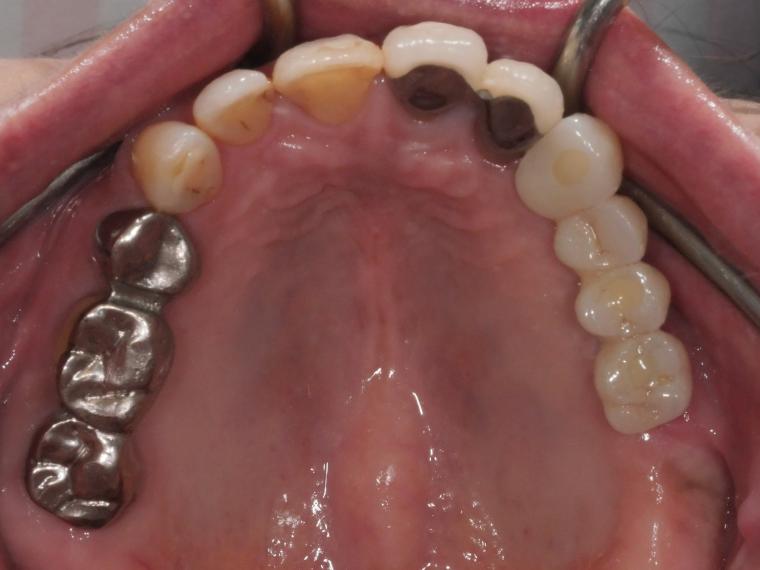

AFTER

ご来院時から欠損状態だった左上第一小臼歯から第一大臼歯も含め、欠損補綴についてお話させていただき、

インプラントでの治療を選択されました。